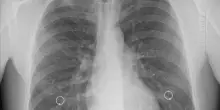

Una nuova molecola contro la pressione alta: è la prima svolta in 20 anni

Per la prima volta in 20 anni, una nuova molecola ha dimostrato di ridurre in maniera significativa la pressione arteriosa sistolica nei pazienti con …